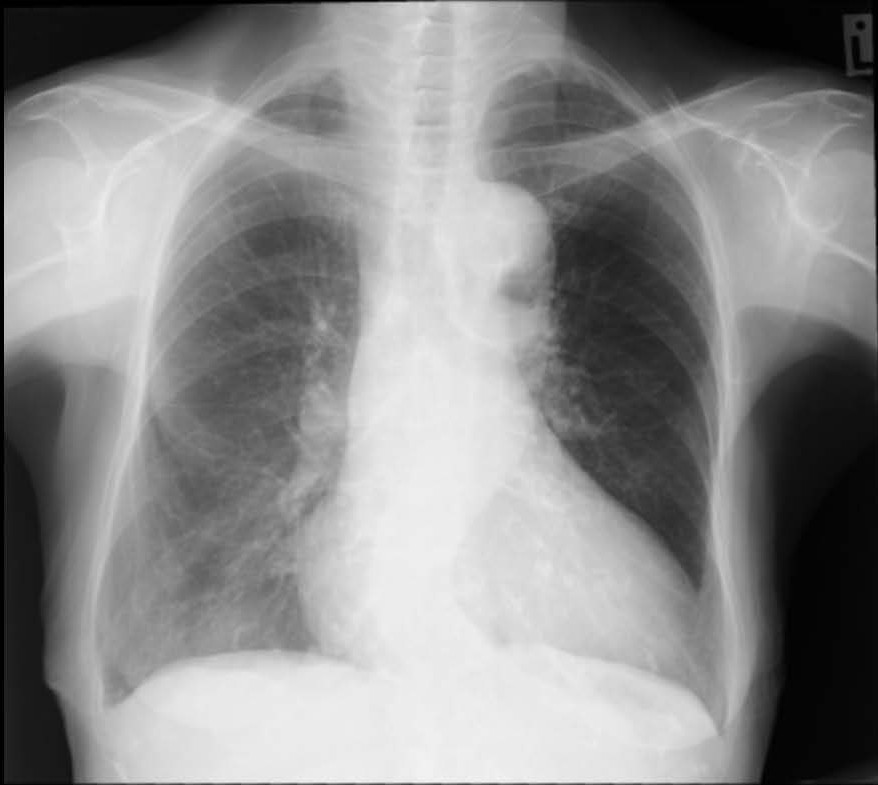

An 86-years-old woman presented with abdominal discomfort and a mass-like sensation. Abdominal ultrasound revealed an abdominal aortic aneurysm (AAA), which was confirmed by CTA. She was hemodynamically stable with no signs of rupture. Physical examination showed peripheral pulses palpable bilaterally, and the case was planned for elective endovascular aneurysm repair (EVAR) under general anesthesia.

CTA demonstrated a fusiform infrarenal AAA measuring 65–68 mm with partial mural thrombus but a thrombus-free proximal neck. The neck measured 19 mm in length, tapering from 19 to 17 mm with mild (≈46¡Æ) angulation and partial mural calcification. Diffuse aorto-iliac calcification was noted with >70% stenosis and tortuosity of the left common iliac artery, while the right iliac axis appeared relatively straight. RCFA and LCFA diameters were 9.4 mm and 7.6 mm.